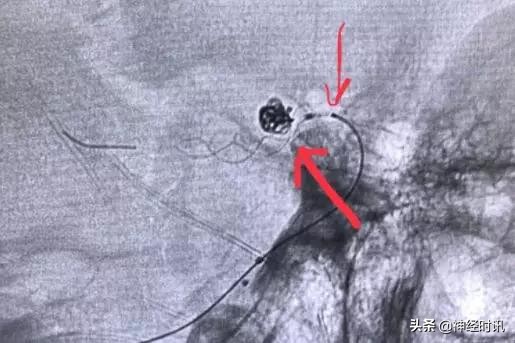

通过几次尝试释放,我们基本摸准了支架头端的定位,然后半释放支架(只保留尾端瘤颈部小部分,箭头),这样可以保证填塞更致密。填入3个Axium弹簧圈后,我们完全释放支架。

点击图片可查看大图详情

换一个角度看:绿色虚线代表颈内动脉边缘,红箭头为支架的显影丝,是不是正好平齐呢?